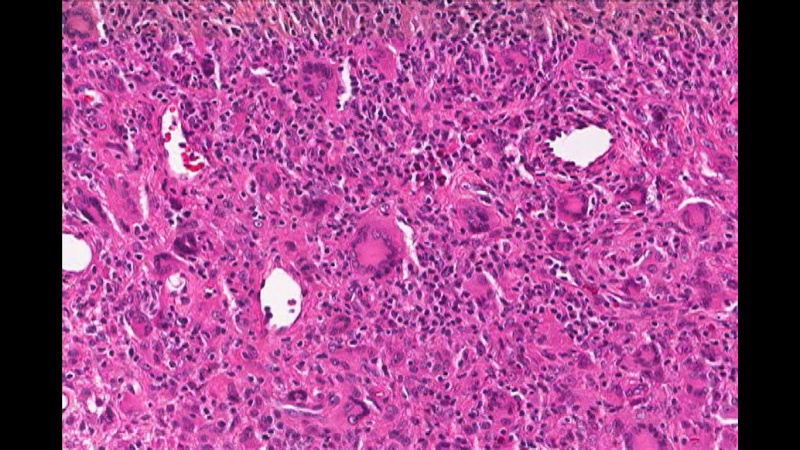

Image 1: Touton Giant Cell, a foamy lipid laden macrophage. Image courtesy of Dr. William Morris, M.D.